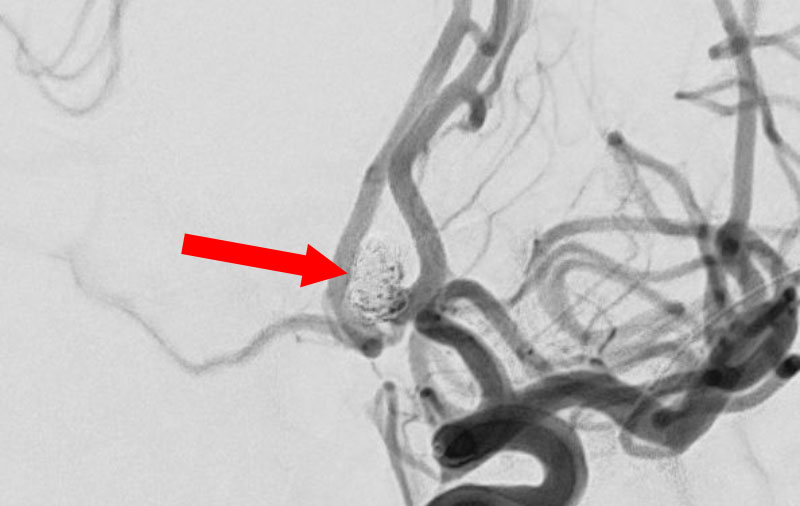

No.1595 手術前